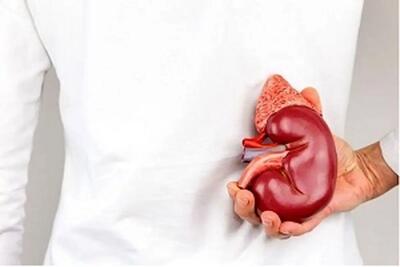

فوق تخصص گوارش و کبد با بیان اینکه کبد وظایف بسیاری از جمله مسمومیتزدایی از متابولیتها، ساخت پروتئین و تولید آنزیمهای مورد نیاز برای هضم غذا، را برعهده دارد، گفت:بهترین راهکار مقابله با کبد چرب اصلاح سبک زندگی و انجام فعالیتهای ورزشی است.